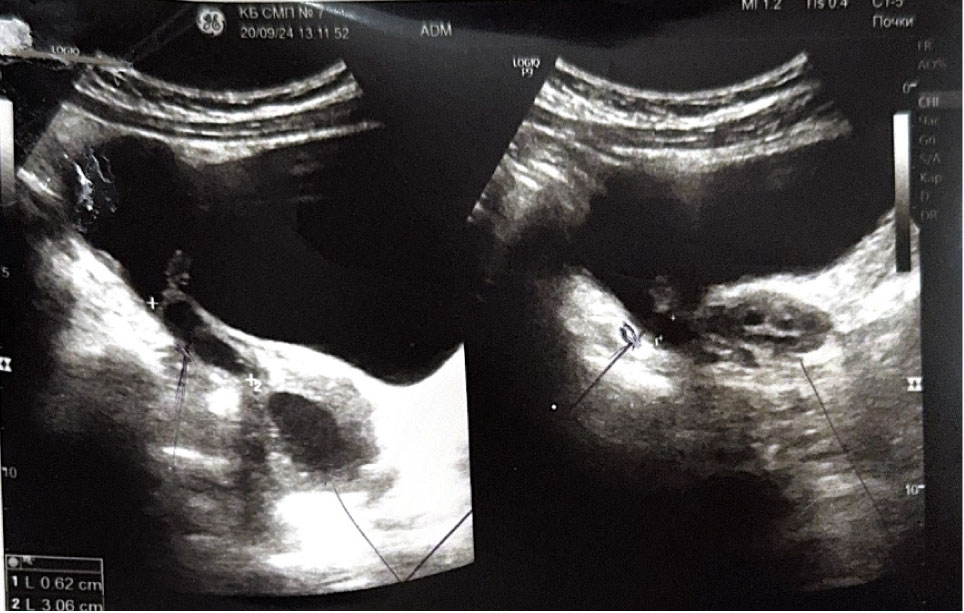

На 6-е сутки послеоперационного периода выполнено УЗИ органов малого таза: тело матки 39 × 23 × 34 мм, незначительно смещено вправо, миометрий однородной структуры. Толщина эндометрия 4 мм, соответствует фазе пролиферации. Яичники нормальных размеров, структура с фолликулярным аппаратом, соответствующим возрастной норме. Заключение: структурные изменения не выявлены (рис. 6).

Рис. 6. Ультразвуковое исследование. 6-е сутки послеоперационного периода